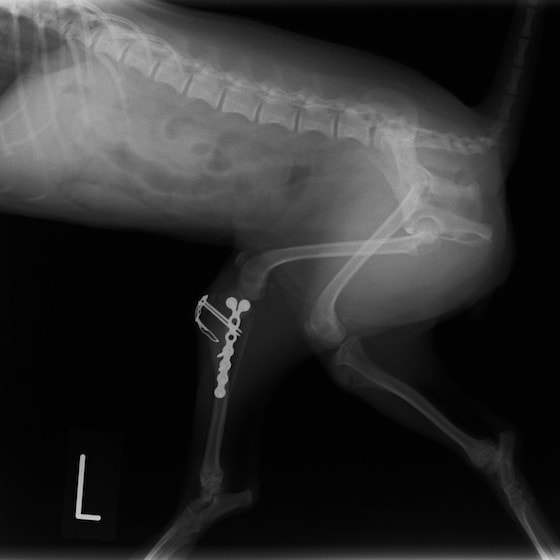

症例:交通事故による椎体脱臼

柴犬:9歳、避妊雌

交通事故直後、胸腰部に激しい疼痛、両後肢に完全麻痺を認め、シェフシェリントン徴候を呈していました。レントゲン検査において、第11-12胸椎間の脱臼が認められました。

脊髄の減圧、脊柱管の再構築・安定化を目的に、片側椎弓切除術およびMatrixMANDIBLE Plateによる椎体固定を実施しました。

隣接椎体を架橋するようにプレートを設置しました。

術後レントゲン写真